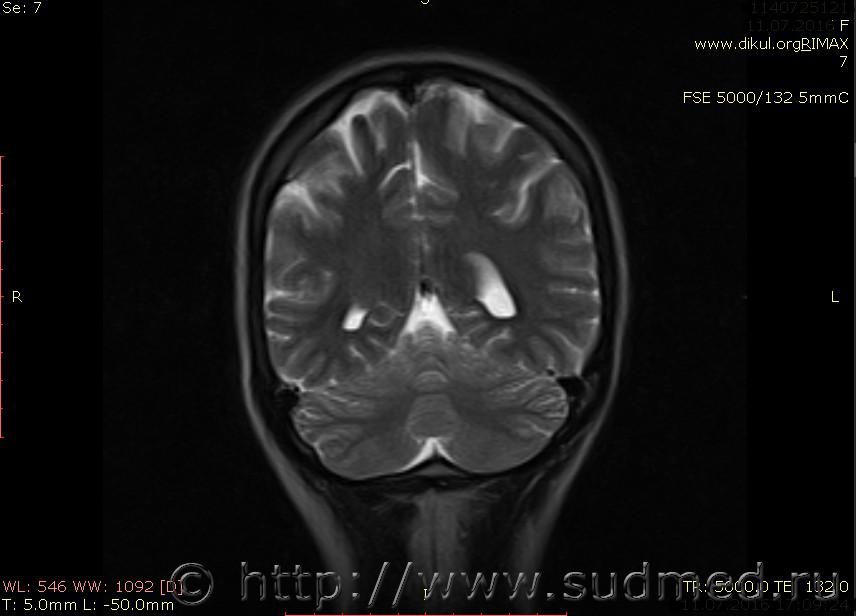

МРТ головного мозга показало: МР-данных за наличие очаговых изменений в веществе головного мозга на момент исследования не выявлено. МР-признаки нарушения соотношения в атланто-осевом суставе. Определяется ассиметрия положения зубовидного отростка С2 относительно боковых масс С1(справа 6,5; слева 4 мм.)

Сама по себе эта информация даёт основания подозревать вывих первого шейного позвонка, но однозначно не свидетельствует о наличии вывиха. Нужно смотреть на снимках наличие реакции со стороны мягких тканей, в т.ч. связочного аппарата, нужно анализировать особенности неврологической патологии, её динамику и проч.

Запрошен электронный вариант снимков из учреждения, где делалось МРТ. Т.к. с самого снимка делать копии не получается,очень мелкие кадры. Завтра попробую вставить в сообщение. (Но СМЭ снимок не смотрел, смотрел только мед.карту, в которой находилось описание МРТ).

Посмотрите пожалуйста снимки, надеюсь на них видны позвонки С1,С2?

Прошу прощения, попробую снова прикрепить файлы. Данные учреждения и пациента убраны.